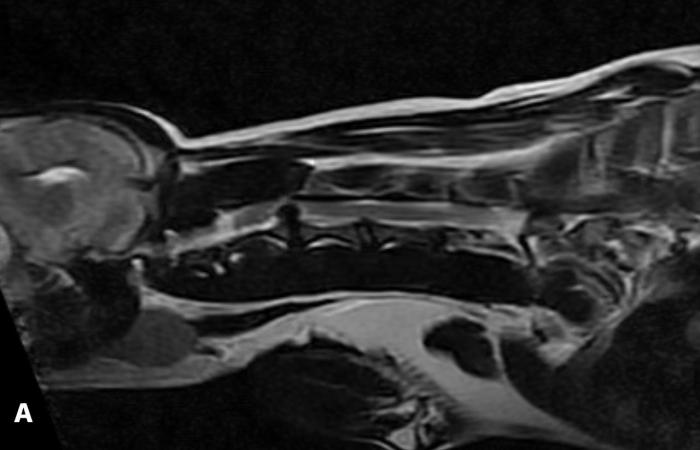

Se indicó una resonancia magnética (RM) de columna cervical bajo anestesia general. El estudio evidenció una extrusión discal a nivel C2-C3 con ocupación del 90 % del canal medular y desplazamiento dorsal de la médula espinal. Se observó hipointensidad del material discal en secuencias T2 (Figura 1A-C), y una leve señal intramedular compatible con edema. Dada la gravedad de la compresión, se indicó cirugía descompresiva urgente.

Figura 1. Resonancia magnética cervical donde se observa la severidad de la compresión medular por la extrusión discal C2-C3. (A) Corte sagital en T2. (B) Corte coronal en T2. (C) Corte axial en T2.